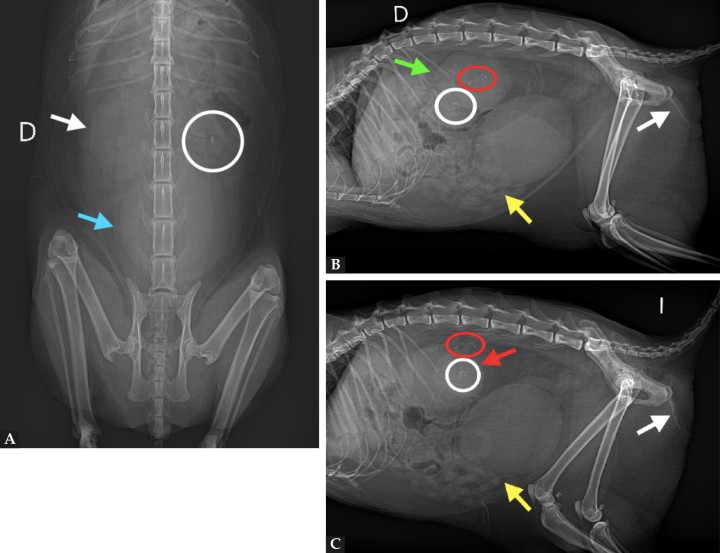

Se observó distensión marcada de la vejiga de la orina con presencia de efecto masa, y desplazamiento craneal y ventral del paquete intestinal. En ambas proyecciones laterales (Figs. 2B y 2C) se visualizó la presencia de pequeñas estructuras de opacidad mineral, forma irregular y bordes mal definidos en la luz vesical. Además, en el interior de la uretra distal se apreció abundante cantidad de material mineral alcanzando una longitud de 2,8 cm. Se vio también un aumento moderado del tamaño del riñón derecho (3,5 veces L2) (Fig. 2A). En la proyección lateral izquierda (Fig. 2C), caudal y dorsal al riñón derecho, en retroperitoneo, se observaron varias estructuras de opacidad mineral, de pequeño tamaño (en torno a 2 y 5 mm), amorfas y de bordes bien definidos. El riñón derecho presentaba un tamaño normal, con bordes irregulares y una estructura de opacidad mineral, redondeada, de bordes irregulares y 8,2 mm en pelvis renal.

Mismas radiografías que en la Figura 1. En la radiografía ventrodorsal de abdomen (A) se observa distensión marcada de la vejiga de la orina (flecha azul), un aumento moderado del tamaño renal derecho (flecha blanca) y la presencia de mineralizaciones en proyección renal izquierda (círculo blanco). En las proyecciones laterales (B y C) se observa una distensión marcada de la vejiga de la orina con desplazamiento craneal y ventral del paquete intestinal (flechas amarillas). Además, se aprecia un aumento marcado del tamaño renal derecho (flecha verde) y mineralizaciones en proyección renal (círculos blancos) y ureteral (círculos rojos). El riñón izquierdo presenta bordes irregulares y tamaño dentro de la normalidad (flecha roja). La uretra distal contiene abundante material mineral en su interior (flechas blancas).

El conjunto de los hallazgos encontrados incluyó como principal diagnóstico diferencial una obstrucción uretral por presencia de abundante material mineral en la uretra distal, con distensión grave de la vejiga de la orina y pequeñas estructuras minerales en su interior compatibles con urolitos.

Por otro lado, la renomegalia derecha y la presencia de estructuras minerales en proyección de uréter derecho podrían corresponder a una hidronefrosis secundaria a una obstrucción ureteral por ureterolitos.

En el riñón izquierdo, los bordes irregulares y la presencia de mineralizaciones/ renolitos en su parénquima y pelvis renal fueron cambios sugestivos de nefritis intersticial crónica.